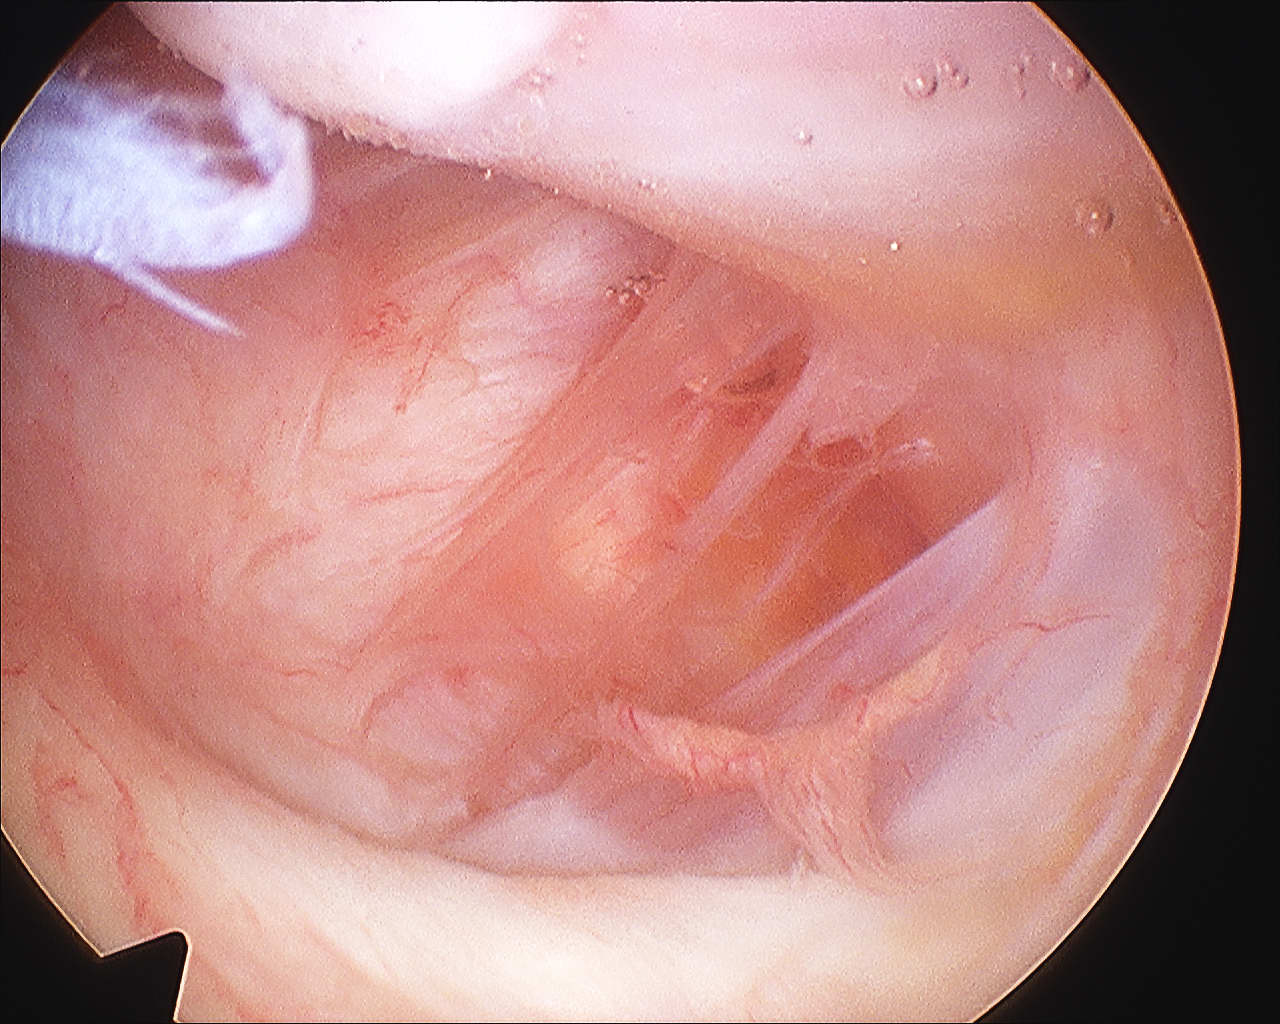

Arthroscopy

Normal insertion onto humeral neck

Abnormal

Isolated HAGL